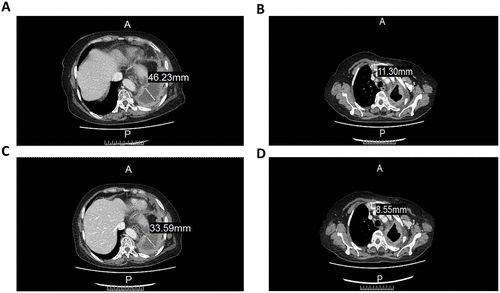

一项于2022年5月3日发表于《Cell Transplantation》上的研究中,报道了采用改良后的CAR-NK疗法治疗晚期非小细胞肺癌患者的病例分析。

经3周期的治疗后,CT图像显示细胞疗法在治疗肿瘤方面具有一定的疗效。具体来说,左肺包裹的胸腔内液体从46.22mm减少到 33.59mm(图 2A ~2C),而前气管-后腔静脉间质区域的淋巴结从11.3mm减少到8.55mm(图2B~2D)。